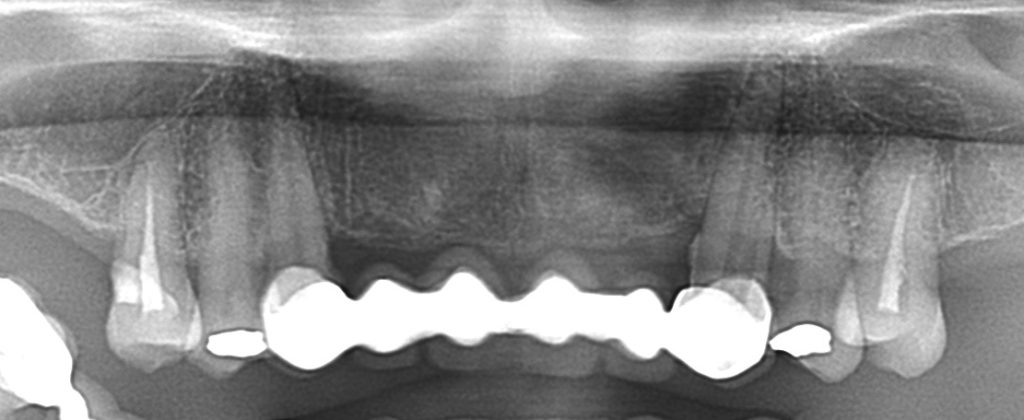

症例140代 男性 主訴 左右臼歯部欠損の為、奥歯で噛めない 前歯がグラつく

治療前

治療後

奥歯でしっかり噛めるようにインプラントを計画・提案。

前歯の長いブリッジは力学的に負担がある為、支えとなるインプラントを配置。

右上小・大臼歯部は、骨高不足の為、ソケットリフト(上顎洞洞底膜挙上術)を適用。

約5ヶ月間の治療期間を経て、全てジルコニアを装着し終了。

リスクとしては外科的侵襲がある。デメリットは、保険外診療の為、経済的負担がある。

費用 340万(税込)(オペ・仮歯・最終補綴物まで含む)